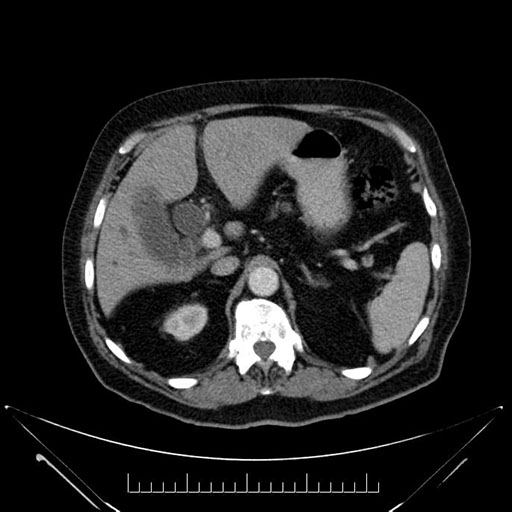

Imaging Analysis

Look through the patient's CT scan to identify any areas of concern for the necessary procedure.

Based on your CT findings, which issue(s) would give reason for "planned slowing down moment(s)" in this case?